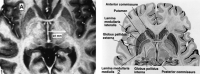

A fast spin-echo inversion-recovery (FSE-IR) sequence is described for its utility regarding surgical planning for patients with Parkinson's disease (PD) who are undergoing microelectrode-guided internal globus pallidus (GPi) ablation. Images from thirty-seven adult patients with PD were reviewed and visualization of the GPi, globus pallidus externa (GPe), and the intervening lamina was noted. High-resolution images were acquired from all patients despite the external hardware and the patients' movement disorder. In all cases, the conventional surgical trajectory, determined indirectly by a fixed measurement from the anteroposterior commissure line, was modified by the ability to visualize the GPi and optic tract directly. This sequence facilitated accurate stereotactic targeting.